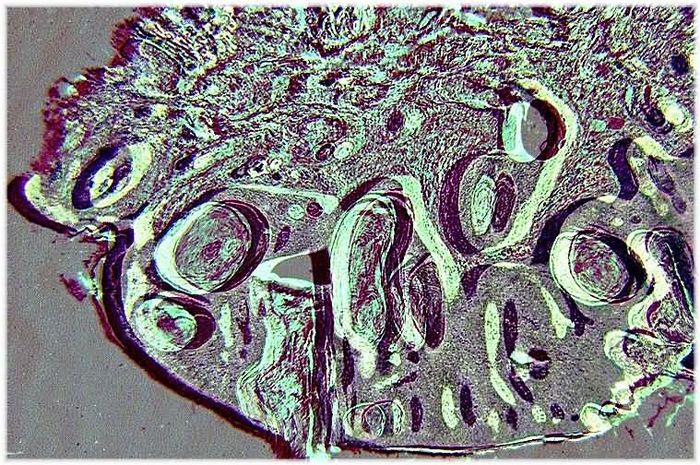

En vignette j'ai cru voir de la caligraphie arabe, non c'est pas l'heure de l'apéro, la bière c'est pour plus tard!

Sont-ce des algues sur une plage Jacques?